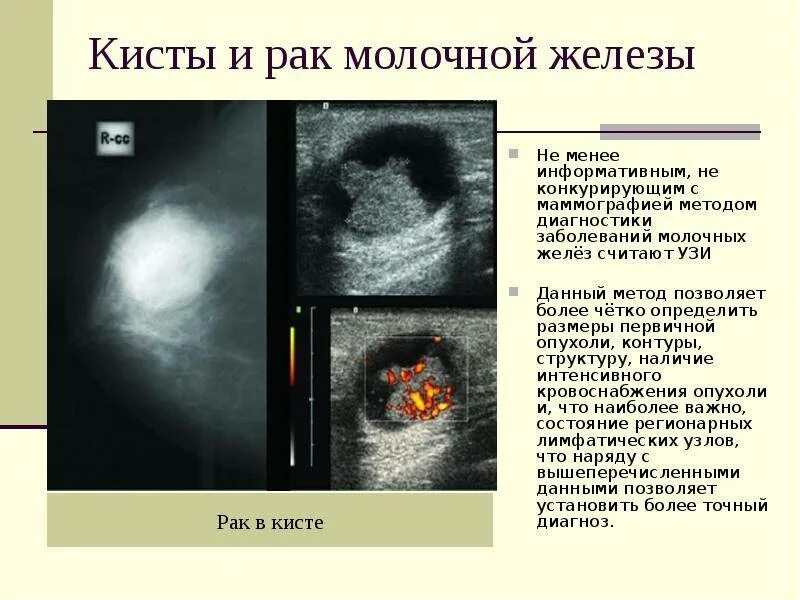

Петрокливальная менингиома. Менингиома доброкачественная. Злокачественные заболевания молочных желез. Новообразование молочной железы. Злокачественная опухоль молочной железы. Доброкачественные новообразования молочной железы.

Злокачественные заболевания молочных желез. Новообразование молочной железы. Злокачественная опухоль молочной железы. Доброкачественные новообразования молочной железы. Очаговые симптомы опухоли затылочной доли. Клинические проявления опухоли лобной доли:. Опухоль мозга височной доли симптомы. Опухоль затылочной доли головного мозга.

Гепатомегалия. Симптомы гепатомегалии. Умеренное увеличение печени. Умеренная гепатомегалия. Маммография косая проекция укладка. Маммография молочных желез. Маммография это исследование. Рентгеновская маммография.

Маммография косая проекция укладка. Маммография молочных желез. Маммография это исследование. Рентгеновская маммография. Подчелюстная слюнная железа на рентгене. Сиалография слюнных желез. Рентгенография слюнных желез. Контрастная сиалография слюнных желез.

Глиобластома мультиформная степень 4. Неоперабельная глиобластома головного мозга.. Глиобластома лобной доли мрт. Глиобластома злокачественная опухоль агрессивная. Филлоидная фиброаденома молочной железы УЗИ. УЗИ признаки доброкачественных опухолей молочных желез. Доброкачественная опухоль молочной железы на УЗИ. Опухоль молочной железы на УЗИ.

Филлоидная фиброаденома молочной железы УЗИ. УЗИ признаки доброкачественных опухолей молочных желез. Доброкачественная опухоль молочной железы на УЗИ. Опухоль молочной железы на УЗИ. Хирургическая операция. Эндоскопическая операция. Хирургическое вмешательство. Эндоскоп хирургический.

Типы роста опухолей. Инфильтративный Тип роста. Инфильтрирующий рост опухоли. УЗИ молочных желез фиброаденома. УЗИ молочных желез фиброаденома УЗИ. Фиброзно-кистозная мастопатия молочных желез на УЗИ. Киста молочной железы с пристеночным образованием.

УЗИ молочных желез фиброаденома. УЗИ молочных желез фиброаденома УЗИ. Фиброзно-кистозная мастопатия молочных желез на УЗИ. Киста молочной железы с пристеночным образованием. Злокачественная опухоль. Злокачественные новообразования. Опухолевые заболевания мозга.